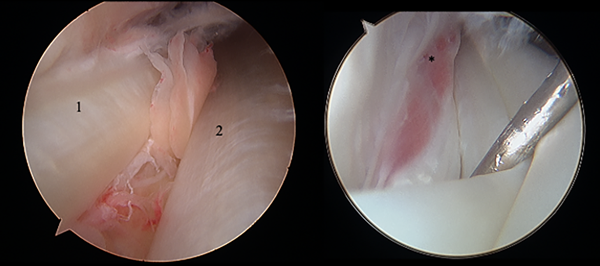

La cirugía para la tendinopatía crónica implica la desbridación del tendón afectado y una tenosinovectomía que puede realizarse de forma abierta o endoscópica. La desbridación endoscópica de la sinovitis facilita la resolución del proceso inflamatorio sin violar la vaina del tendón (fig. 6).7

En la tendoscopia, cada tendón se inspecciona abriendo longitudinalmente la vaina sinovial. El TPL debe explorarse distalmente hasta el túnel cuboideo. Si se encuentra un VMPBB, debe resecarse. Además, permite una visualización clara de una luxación/subluxación o desgarros sutiles que no son evidentes en la resonancia magnética.

Figura 6: Imagen tendoscópica. 1) Peroneo corto. 2) Peroneo largo. *) Peroneo cuarto.

Bojanić et al. informaron sobre ochenta y dos pacientes sometidos a tendoscopia de los tendones peroneos como procedimiento único o adicional a la artroscopía o cirugía abierta del tobillo. Algunas conclusiones de este estudio fueron que el VMPBB, entre otras variaciones anatómicas, se asociaba con roturas del TPB, subluxación intravaina y dolor postraumático en el tobillo posterolateral. No se logró diagnosticar un VMPBB previo a la cirugía por lo que recomiendan prestar especial atención para reconocerla durante la tendoscopia; consideraron que la resonancia magnética por sí sola no debería ser la base para diagnosticar la patología de los TP.37

La tendoscopia es un procedimiento con baja morbilidad y excelentes resultados; la sinovectomía, la lisis de adherencias, la eliminación de exostosis, el diagnóstico y el tratamiento de las variaciones anatómicas pueden lograrse con éxito.38,39